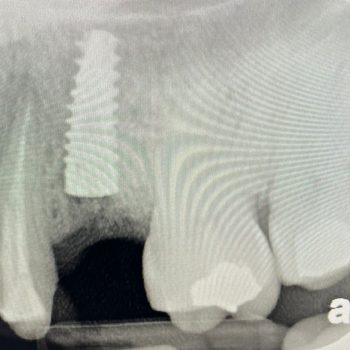

Inmediate load implant + Integros Bone Plus XS

Holatlar

Integros Bone Plus XS foydalanib yangilangan suyak.

Integros Bone Plus XS’dan foydalanib tezkor o’rnatish implanti

Bone regeneration using Integros Bone Plus XS